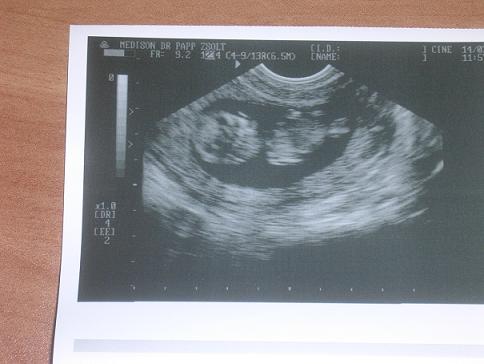

Várjuk a uh képet. Tényleg nagyon cuki a kislányod a képen.